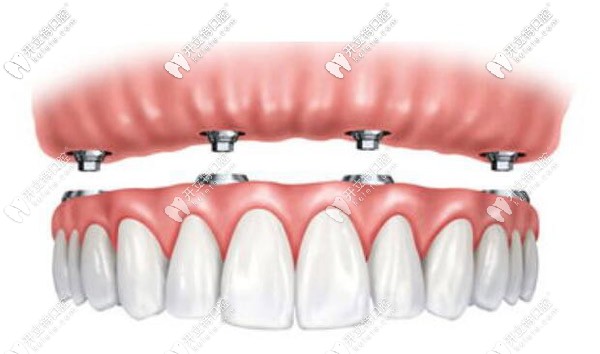

半固定和全固定還是有區(qū)別的:

半固定種植圖示

半固定就是可以還是可以摘卸的,半固定式的是需要三餐后取下來清潔的,全固定就像自己的牙齒一樣,只需要飯后刷牙進行清潔就好。